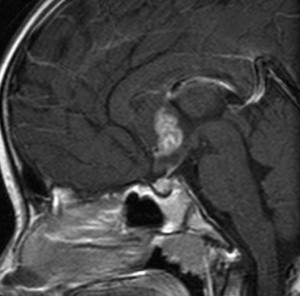

血清HCG-beta 4.5mIUで,下のMRIに見られるように第3脳室(視床下部)のグリオーマ(毛様細胞性星細胞腫)と見間違うような腫瘍でした。下垂体柄は太くなっていないし下垂体のサイズも普通です。もちろん水頭症もありませんので,開頭手術で生検をしてgerminomaの診断を得ました。

上のMRIで視神経交叉が腫大しているのが解りますが,下のMRI CISS画像では更に明らかです,左右の視神経と視交差と視索が腫大していました。視力を計ったら,右0.6,左1.5でいびつな視野欠損がありました。腫瘍はのう胞形成しながら左の視床下部から大脳基底核にも浸潤していました。